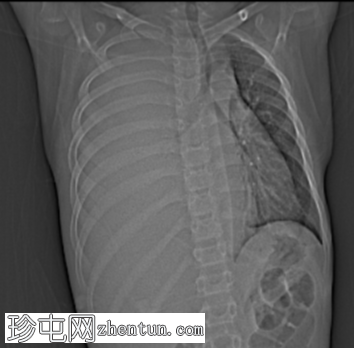

定位扫描图像发现:

右肺野完全影,伴有轻度向对侧(左侧)纵隔移位,提示大量胸腔积液或大型占位性病变。